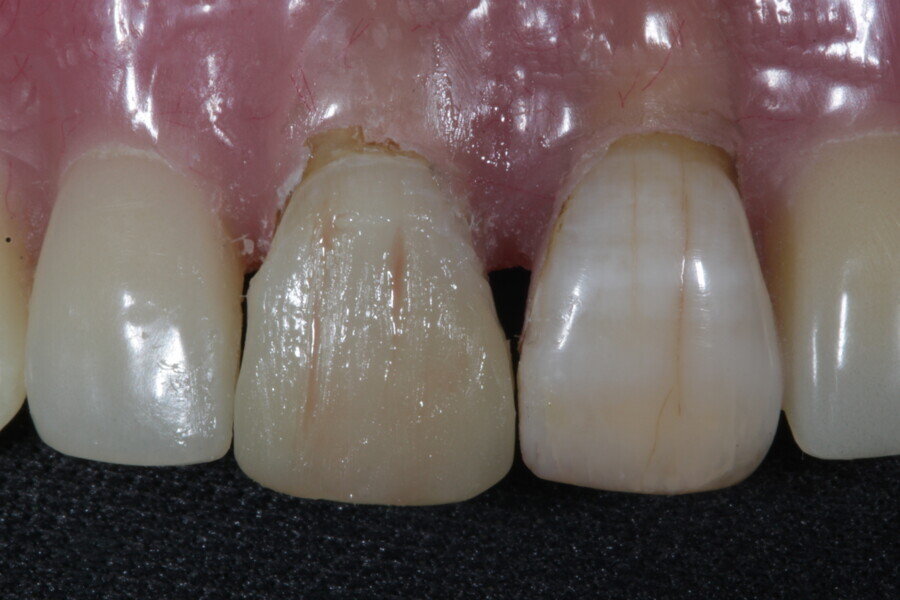

1. functional and aesthetic reconstruction of a maxillary anterior tooth using fibre-reinforced flexible micro-posts after endodontic treatment (Figs. 3–20);

Example 1—showing functional and aesthetic reconstruction of a maxillary anterior tooth using fibre-reinforced flexible micro-posts after endodontic treatment.